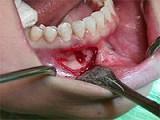

问题 组图为牙瘤的外观及X 线表现,有关此病的描述错误的是 ( )

选项 A.绝大多数为恶性 B.生长缓慢,早期无自觉症状 C.由牙胚组织异常发育增生而形成 D.X 线可见类似发育不全牙的影像 E.多见青年人

答案 A